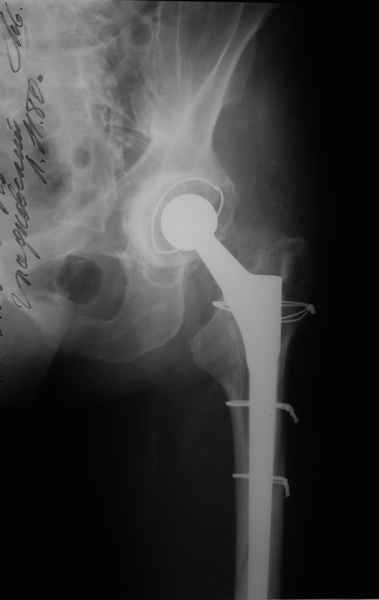

Произведено закрытое удлинение ножки эндопротеза с помощью ретроградного интрамедуллярного стержня. Продолжительность операции 3 часа. Два из них закрытое восстановление длины бедра диистрактором

таз-бедро.

А нельзя ли увидеть и профиль бедра на всем протяжении, т.е. и весь протез, и весь стержень? И фас бы с коленом.

новые снимки

Пациента удалось осмотреть недавно. Достигнутый результат сохраняется. Перелом бедра сросся. Конечность опорная и безболезненная, ходит без трости. Ножка, похоже, реинтегрировалась, как и надеялись. Снимки и фото в приложении. Комментарии приветствуются.

Надо ли что-то делать дальше, как полагаете? Убрать винты? Убрать "удлинитель ножки"? Или оставить все, как есть? Спасибо заранее.